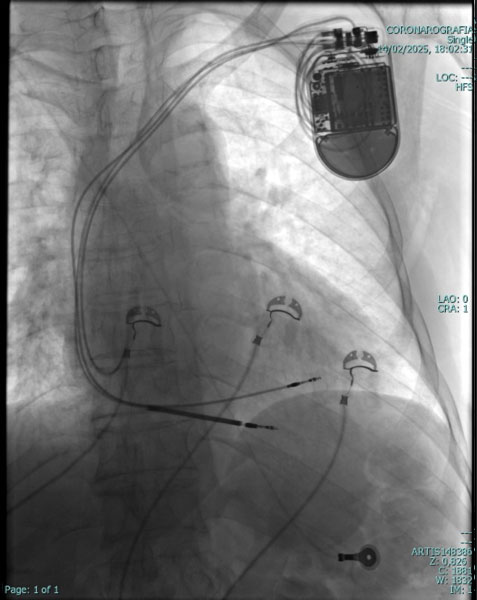

Il Pace Maker è un piccolo apparecchio elettronico che viene inserito nel corpo del paziente mediante una breve incisione, solitamente sotto la clavicola sinistra. Il Pace Maker è collegato al cuore mediante uno o due fili elettrici (detti “cateteri”), introdotti in una vena della spalla.Il pacemaker interviene in aiuto del cuore quando questo batte troppo lentamente; tuttavia non impedisce al cuore di funzionare autonomamente nei momenti in cui batte in modo regolare.

Il Pace Maker è costituito da una piccola scatola di metallo liscio e leggero; le dimensioni e il peso variano a seconda del tipo e delle caratteristiche; mediamente ha una forma rotondeggiante, misura tra 5 e 6 cm da un lato, tra 4 e 5 cm dall'altro e ha uno spessore tra i 7 e i 9 mm; il peso oscilla tra 20 e 30 grammi. La scatola contiene un minuscolo computer e una batteria, che può durare, a seconda dell'uso che se ne fa, fino a 12 anni; attraverso uno o due elettrodi, a seconda delle necessità, invia al cuore piccolissimi impulsi elettrici in grado di aumentare, quando è necessario, i battiti cardiaci.

Gli impulsi elettrici trasmessi dal Pace Maker al cuore sono di bassissima intensità e non vengono assolutamente avvertiti dal paziente. Il Pace Maker viene inserito mediante una semplice procedura: in anestesia locale si pratica una piccola incisione della pelle, di pochi centimetri, nella regione alta del torace, sotto la clavicola sinistra. Si cerca quindi una vena per l'introduzione dei cateteri, che vengono guidati fino al cuore, controllandone il percorso mediante la radioscopia; dopo aver controllato che i parametri elettrici siano regolari, i cateteri vengono collegati al Pace Maker che viene infine inserito in una piccola tasca sotto la pelle; tutto ciò avviene in modo del tutto indolore.